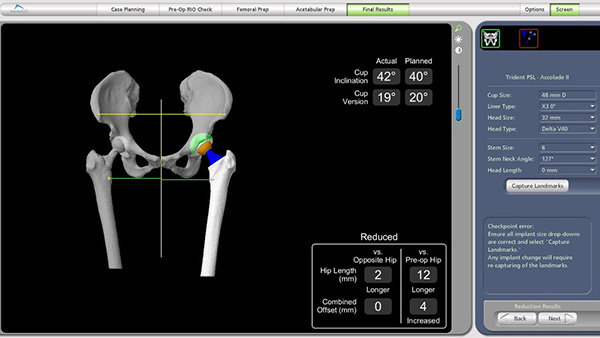

安放假体后校验显示左髋较术前长12mm,较对侧长2mm。肢体长度差异达到毫米级。

术后复查床旁骨盆X光片显示左髋假体位置:髋臼外展角、前倾角、假体偏心距及肢体长度均与术前计划一致。